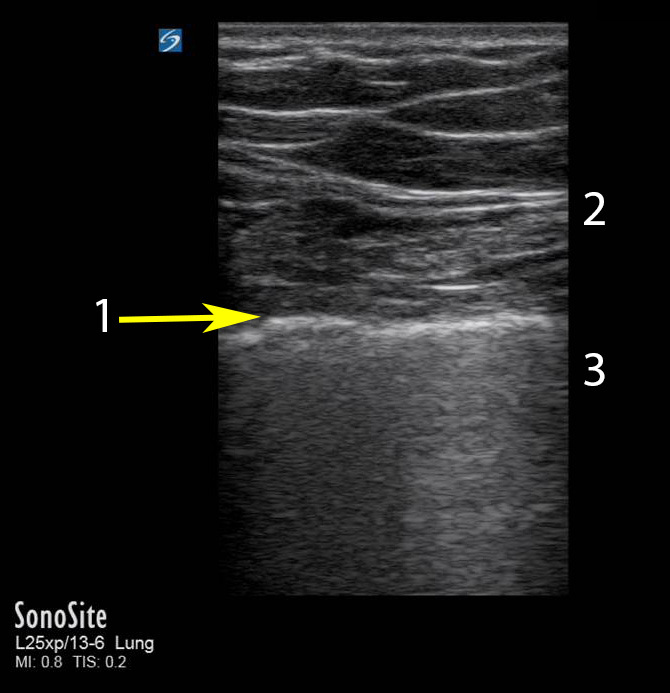

Bild: Lunge, Seashore-Sign

Pleuraspalt

Sea

Shore